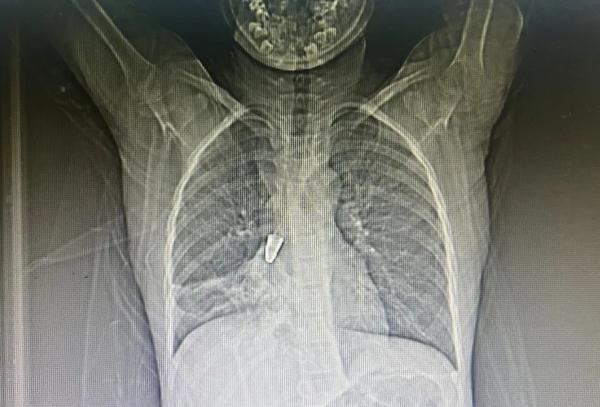

肺部CT检查显示,笔头卡在小杰右侧的支气管深处,仅剩直径2毫米的小孔维持空气流通,影响孩子正常呼吸。随后,小杰被紧急转到医院的耳鼻咽喉科接受治疗。

拍片可清晰看到,男孩支气管内有金属笔头。“金属笔头很易被呛进气道,但是不容易取出来。”耳鼻咽喉科副主任医师李栋介绍,金属笔头是圆锥形,小头朝下、大头朝上,和支气管卡得严丝合缝,很难夹取到,夹取时还要控制好力度,以防对气管造成二次损伤。